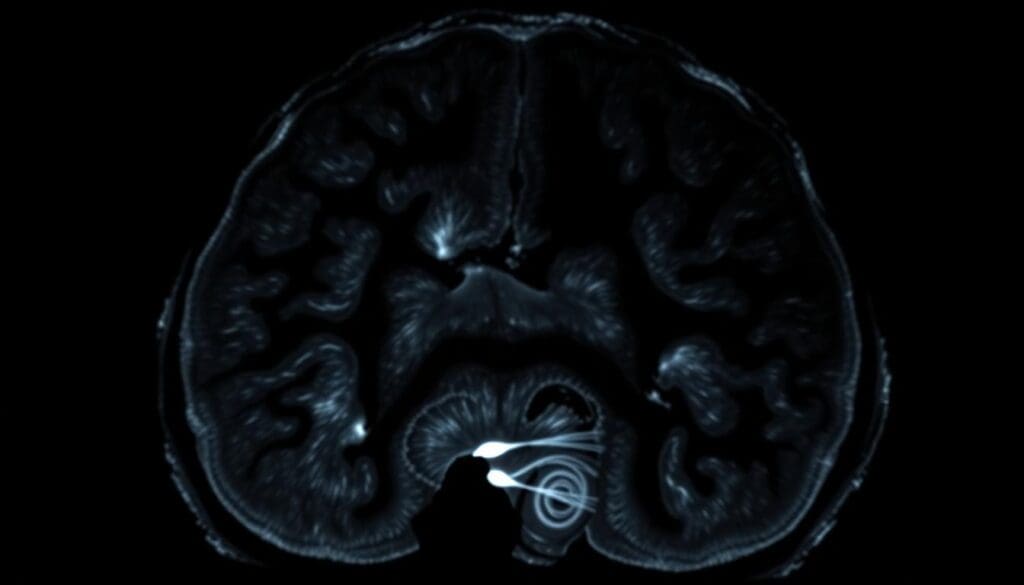

Appearance of Hyperechogenic Regions on Ultrasound

On an ultrasound, choroid plexus cysts look like hyperechogenic regions. These are spots that shine brighter than the rest. This makes it easy for doctors to find and check them out. Thanks to today’s ultrasound tech, these cysts can be seen and tracked accurately.